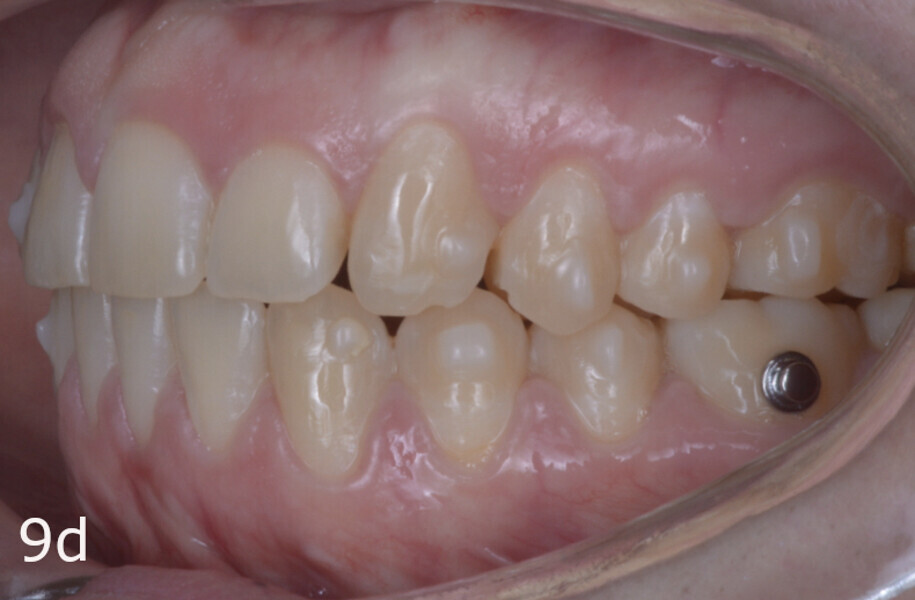

The 23-year-old dolichofacial female patient complained of not being able to chew properly. Facial examination showed a convex profile, an enlarged lower facial height, and a skeletal Class III malocclusion (Figs. 1–3). Intra-oral examination revealed an Angle Class III right subdivision malocclusion, anterior open bite, no overjet and a maxillary dental midline deviated about 3 mm to the right compared with the mandibular dental midline (Fig. 4). The panoramic radiograph confirmed previous extraction of the maxillary right first premolar and the presence of all four third molars (Figs. 5 & 6).

The treatment objectives included closing the anterior open bite, achieving a bilateral Angle Class I relationship and a proper overjet and overbite, correcting the midline discrepancies, and achieving a profile harmonisation. The treatment plan consisted of orthodontic camouflage treatment with asymmetric distalisation in three of the four quadrants using Invisalign aligners (Align Technology) and third molar extraction. The Invisalign Comprehensive package was chosen, and 63 pairs of aligners were used (Figs. 7–10). Each aligner was worn for 20 hours a day for one week each. The use of Class III elastics on both sides was indicated. Afterwards, ten refinement aligners were needed to improve the interdigitation on the right side (Figs. 11 & 12).

Although Class III elastics tend to extrude the maxillary molars and generate clockwise mandibular rotation, aligners allow us to prevent these complications, since we have better control over tooth movement, enabling us to counteract unwanted dental movements. In this case, an intrusion of the posterior teeth was planned, which would generate anticlockwise rotation of the mandible in an anticlockwise direction. This vertical control led to the closure of the anterior open bite and the reduction of the lower facial height, thereby improving the facial profile.

The total treatment time was 15 months. An Angle Class I relationship was established along with adequate anterior and canine guidance, establishing a functional occlusion. This not only ensures optimal masticatory function but also protects the teeth and the temporomandibular joint from excessive force. Maxillary and mandibular fixed retention were installed at the end of the treatment (Figs. 13–19).